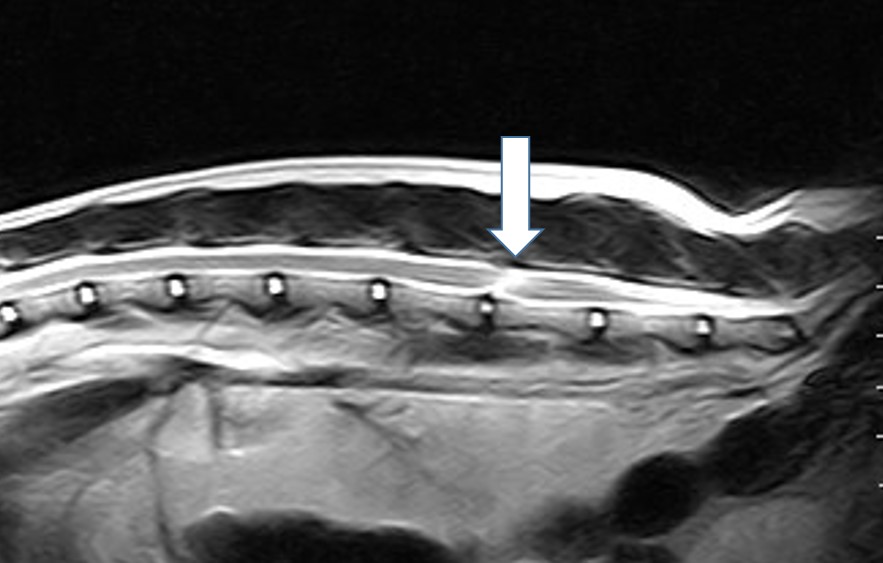

If your cat has a disk disease, which we finally diagnose with a CT or MRI, surgery has to be discussed if the hind legs are paralyzed. This is not so common, but we see patients like this from time to time (Fig 5).

Fig 5: Disk extrusion in a middle aged Siamese Cat

Fig 5: Disk extrusion in a middle aged Siamese Cat